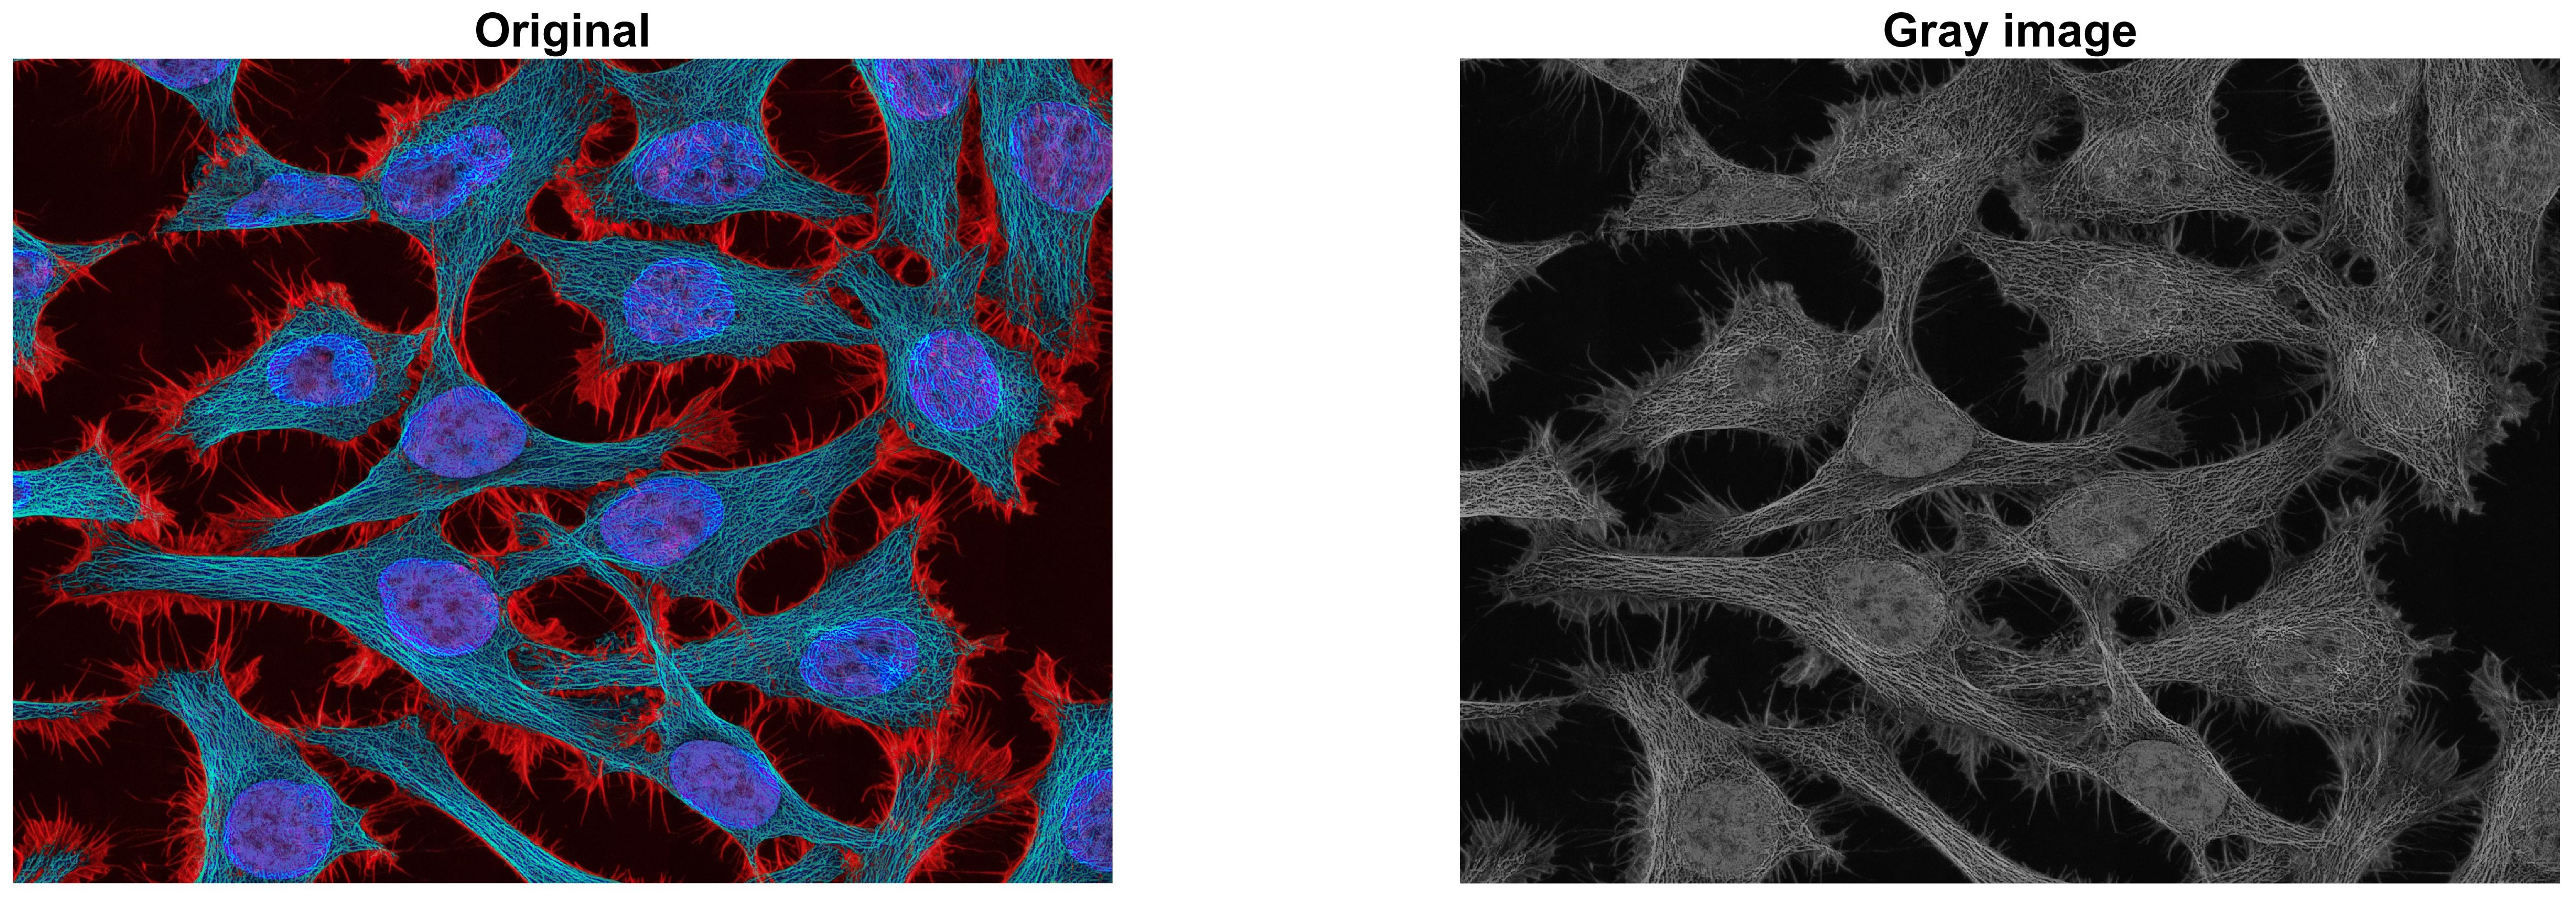

앞의 글 [MATLAB 영상처리 기초 3] 이미지의 픽셀값 다루기 - RGB2Gray 에서 RGB 컬러채널을 갖는

이미지의 grayscale 변환을 수행하였습니다.

그리고 grayscale 변환된 이미지 데이터는 MATLAB에서 기본적으로 uint8 형식을 가짐을 알 수 있었습니다.

( 위 이미지는 본 블로그 맨밑 출처 1에 가셔서 다운로드 받을 수 있습니다. )